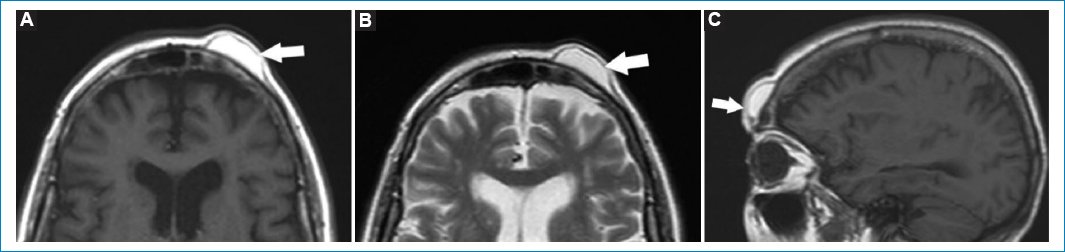

Los lipomas constituyen uno de los tumores benignos más frecuentes. De morfología redondeada y bordes bien definidos, se los aprecia hiperintensos tanto en secuencias ponderadas en T1 como en T2, por su rico contenido en lípidos. Las secuencias con supresión grasa son útiles para valorar la reducción de señal del lipoma (Fig. 14)34.

Figura 14. (A-C) Lipoma del cuero cabelludo, a nivel frontal izquierdo (flechas). Cortes: axial T1 (A), T2 (B) y sagital T1 (C). Se observa como una elevación con señal hiperintensa en su interior, por contenido rico en lípidos.

Los quistes sebáceos son formaciones quísticas bien delimitadas localizadas en la dermis. Si su contenido es rico en lípidos se aprecian hiperintensos en T1 y T2; en cambio, si el contenido es rico en queratina o pelo, puede valorarse como hipointensos/isointensos en T1 e hiperintensos en T2 (Fig. 15)34.

Figura 15. (A-C) Quistes sebáceos con contenido rico en queratina. Cortes: axial T1 (A), sagital T1 (B) y coronal T2 (C). Se muestran distintos pacientes en los que se observan (flechas) formaciones ovoides en el tejido celular subcutáneo, menores a un centímetro, con límites netos, que abomban la dermis. Son isointensos/hipointensos en T1 y T2.